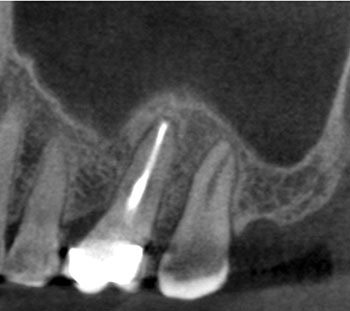

Case 1:A J-shaped lesion

As dentists, we can become desensitized to how important each tooth is to a patient and how impactful we can be in saving one. This patient’s dentist told her that #30 had a vertical root fracture and she needed to have it extracted and replaced with a dental implant. No other treatment options were given. She came independently for a second opinion and said how devastating it would be for her to lose a tooth.

Tooth #30 had a diagnosis of previous root canal treatment with symptomatic apical periodontitis. The mesial root had a classic J-shaped radiographic lesion and a narrow probing defect from the buccal furcation to the root apex. No crack could be seen on what little root surface was visible. The likelihood of VRF, or the possibility of a failing root canal with a chronic apical abscess, were discussed. The latter could be treatable. The plan was to attempt re-treatment after internal inspection for a possible VRF.

Fig. 1: Preoperative PA.